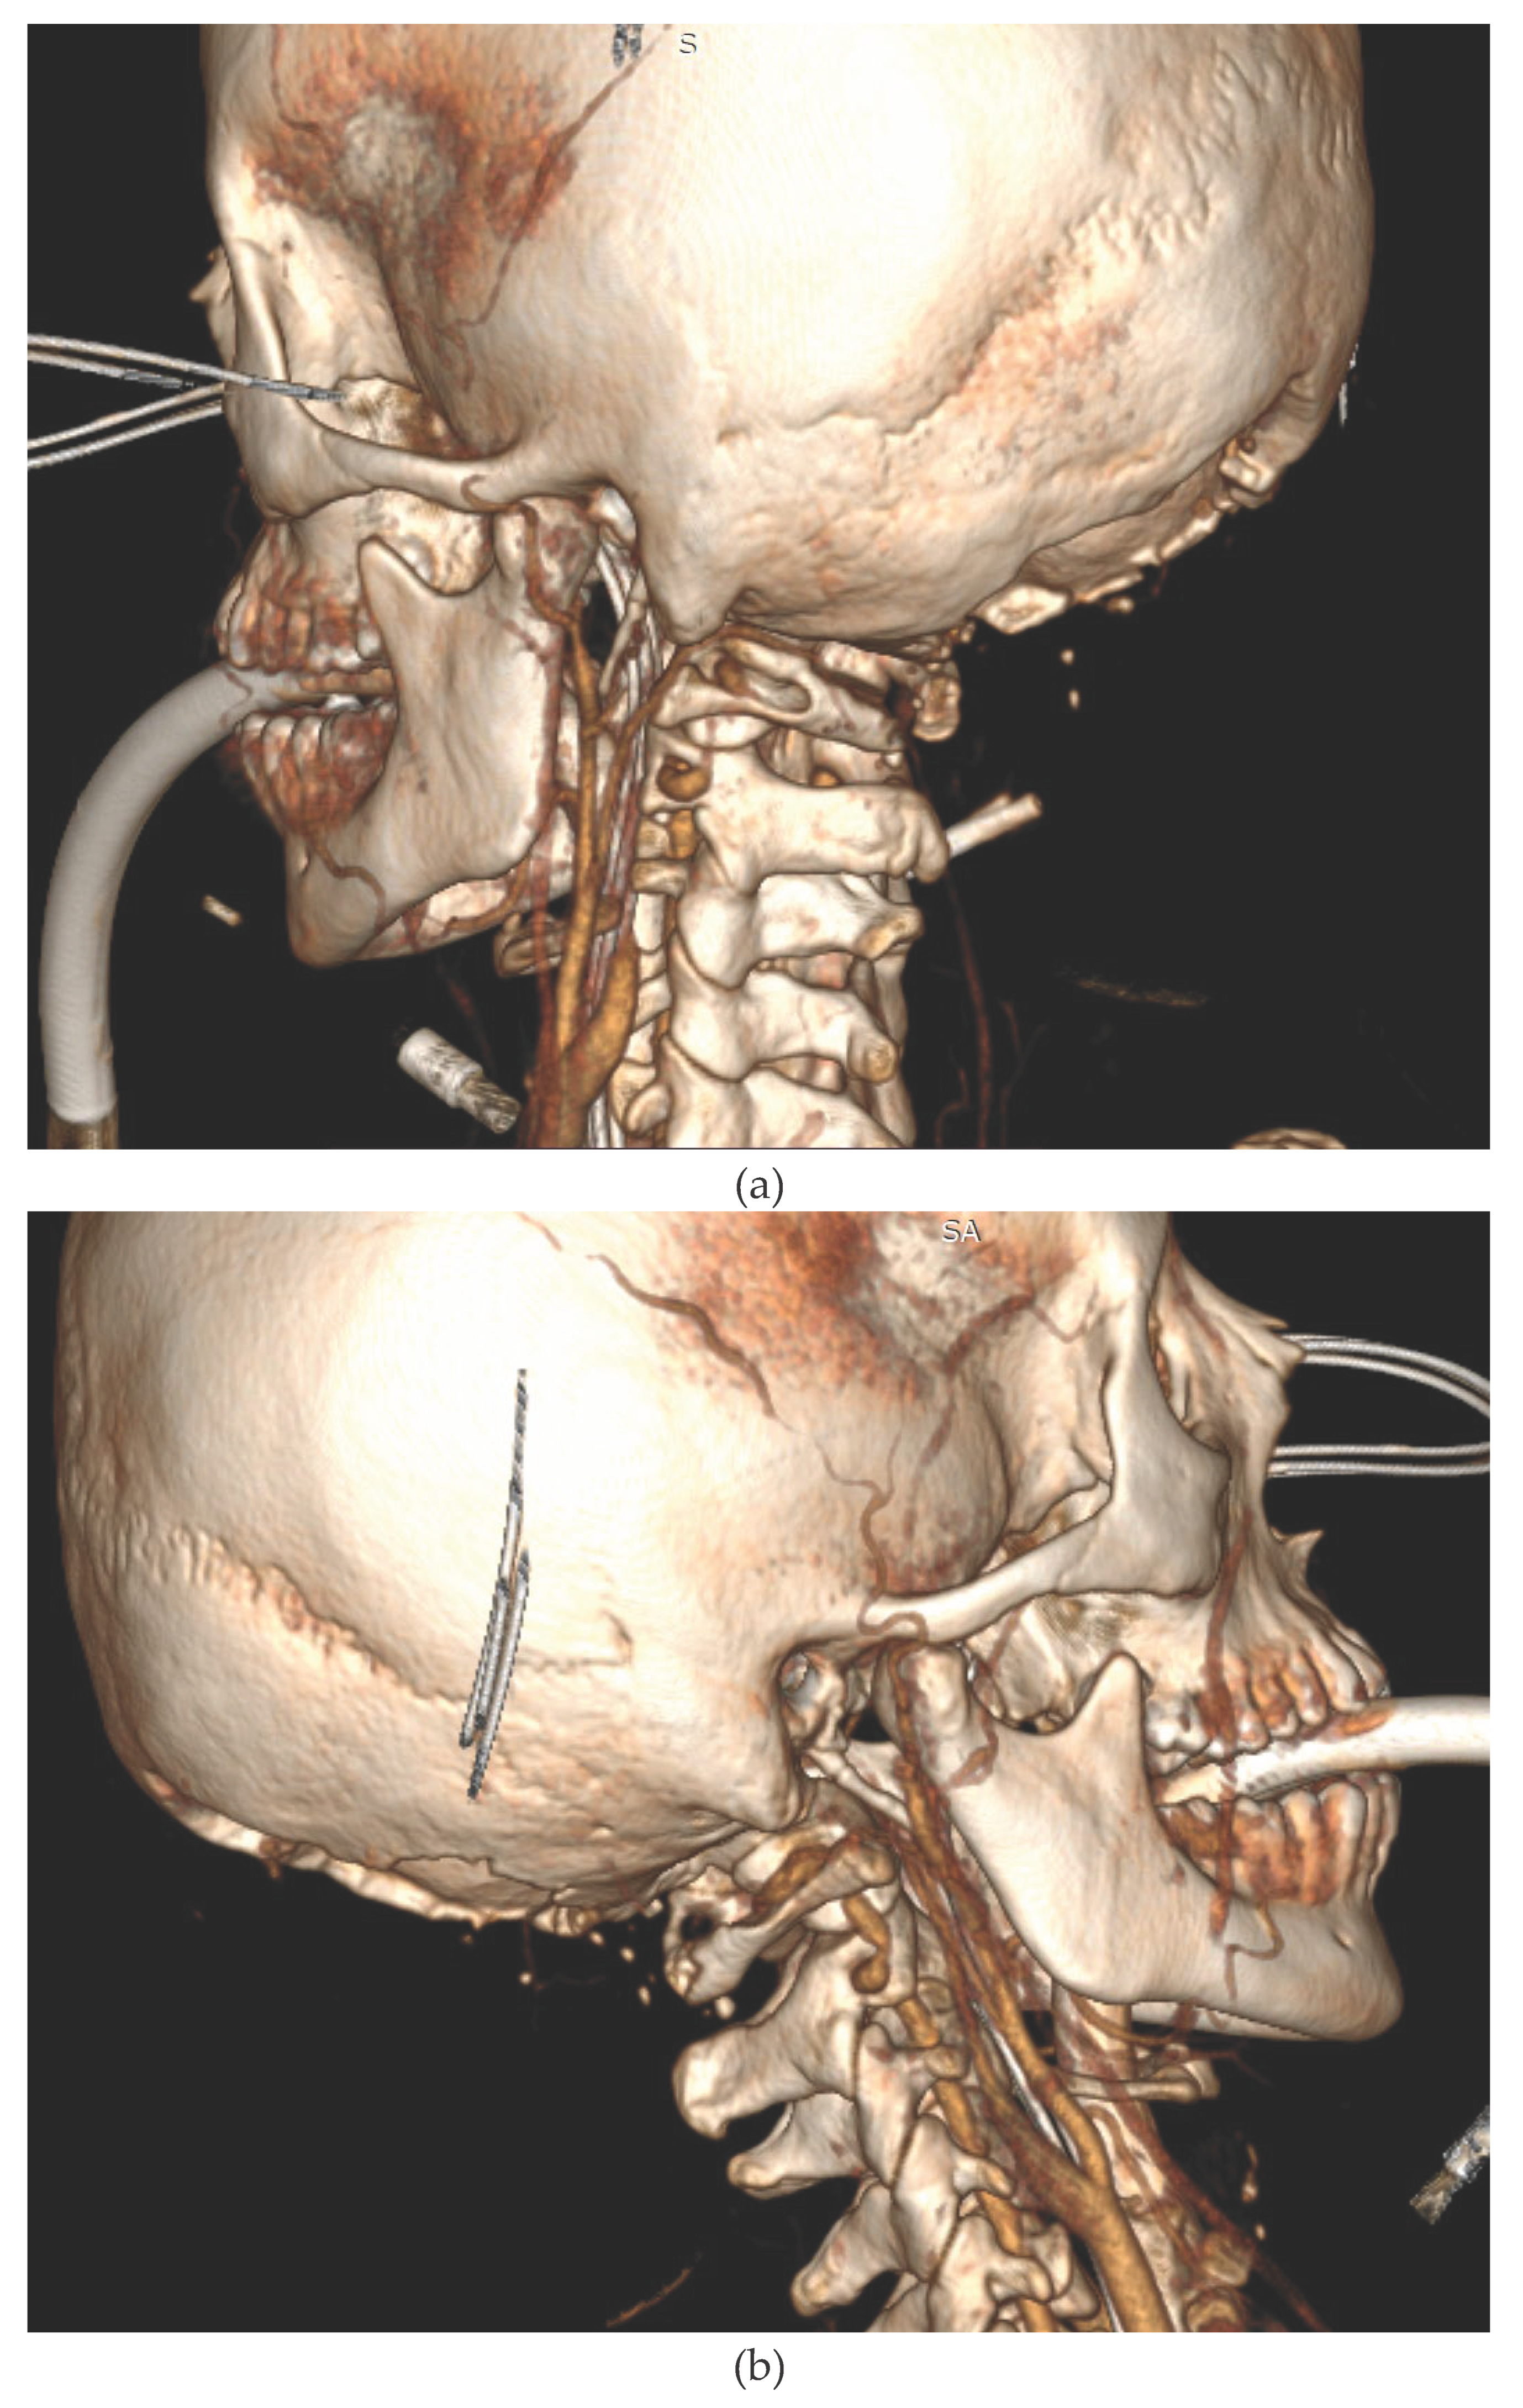

We present the case of a 33-year-old female patient with a diagnosis of AML (Acute Myeloblastic Leucaemia). The patient, was transferred from Haematology Unit to ICU following neurological deterioration. On the basis of the imaging studies performed, the diagnosis was an acute intracranial haemorrhage. Immediately after the CT scan, the patient underwent neurosurgical treatment. After the surgical procedure, he was readmitted to the ICU. Despite the therapy, the patient was diagnosed with the absence of brain reflexes. Among the imaging tests performed, there was a CT scan of the CNS (Figure 1a,b) and CTA (Figure 2a,b), which showed catastrophic brain damage. Then, according to institutional brain death guidelines clinical evaluations and apnoea tests were performed at certain intervals (Current AAN brain death guidelines do not require multiple exams) [10].

Figure 1. Head CT. The examination shows intermediate features of severe cerebral ischaemia. (a) Loss of grey/ white matter differentiation in the supratentorial space with a sign of pseudosubarachnoid haemorrhage. (b) Severe oedema of the posterior fossa structures (despite suboccipital decompression), with completely obliterated basal cisterns and ischaemic-haemorrhagic changes in the brainstem.

Figure 2. Head Computer Tomography Angiography (CTA). 3D reconstruction of the CTA study. (Left file) Left carotid arteries showing contrast flow obstruction in the extracranial segment of the C1 LICA (just behind the LCCA division) and in the extracranial segment of the V3/V4 LVA. (File right) Right cerebral arteries shows contrast occlusion in the extracranial segment of the C1 RICA (before entering the RTCA) and in the extracranial segment of the V.4 RVA.